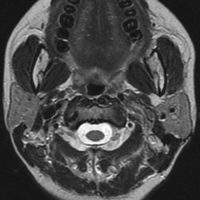

症例:頸静脈孔から頭蓋内へのもの

頸静脈孔を中心に頭蓋底骨の破壊 erosionがみられます。小脳延髄角部に進展して延髄を圧迫しています。聴神経を圧迫して聴力低下で発見された,迷走神経鞘腫です。頸静脈孔内発生のものは脳槽内の迷走神経根から腫瘍を剥離することができます。

手術直後のMRIです。頸静脈孔より深い位置にある腫瘍まで摘出しようとすると,舌咽,迷走,副神経を損傷しますから,最深部の部分だけ残して摘出しました。

手術後14年が経過しますが,無治療で残存腫瘍は縮小しました。術後神経鞘腫の自然経過ではよく観られることです。

ですから,無理して全摘出しない。